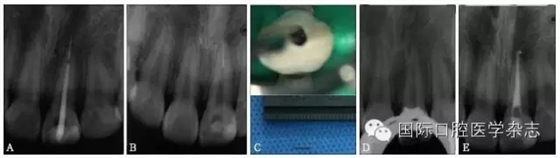

超聲技術(shù)作為經(jīng)典且有效地取出分離器械的方法之一,具有獨(dú)到的優(yōu)勢。超聲工作尖可以在顯微鏡直視下在根管內(nèi)運(yùn)動,且能夠不對稱地去除分離器械周圍的牙本質(zhì),若只在分離器械一側(cè)局部運(yùn)動即能取出分離器械,則有利于保存根管壁較薄一側(cè)的牙本質(zhì),減少牙本質(zhì)的損失。此外,當(dāng)器械分離于根管中下段甚至超出根尖孔,而分離器械較松時,可用超聲工作尖伸入根管內(nèi)分離器械旁邊,利用水流與超聲振動將分離器械帶出根管(圖11)。

A:X線片示上頜中切牙根尖部有一分離器械,器械超出根尖孔;B、C:超聲結(jié)合水流沖洗,有時可意外取出分離器械;D:X線片示分離器械被取出;E:根管預(yù)備并充填至根尖。

圖 11 當(dāng)器械分離于根管中下段甚至超出根尖孔,而分離器械較松時,超聲器械有獨(dú)特的優(yōu)勢